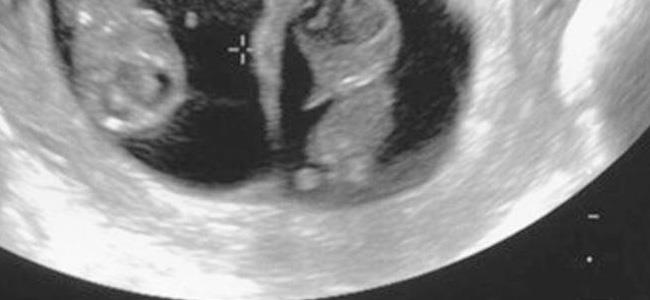

الجريبات: أول علامات الحمل التي يمكن رؤيتها عن طريق الفحوصات هي جريبات الحمل (كيس الحمل)، والتي تبدو بيضاوية الشكل في تصوير الألتراساوند. بعد مرور 4 أسابيع من الحمل يمكن رؤية جريبين (كيسين) إذا كان الحمل بتوأم غير متطابقين. أما التوأم المتطابق فينمو في جريب واحد، ولا يمكن رصدهما قبل الأسبوع الـ5 عن طريق الألتراساوند.